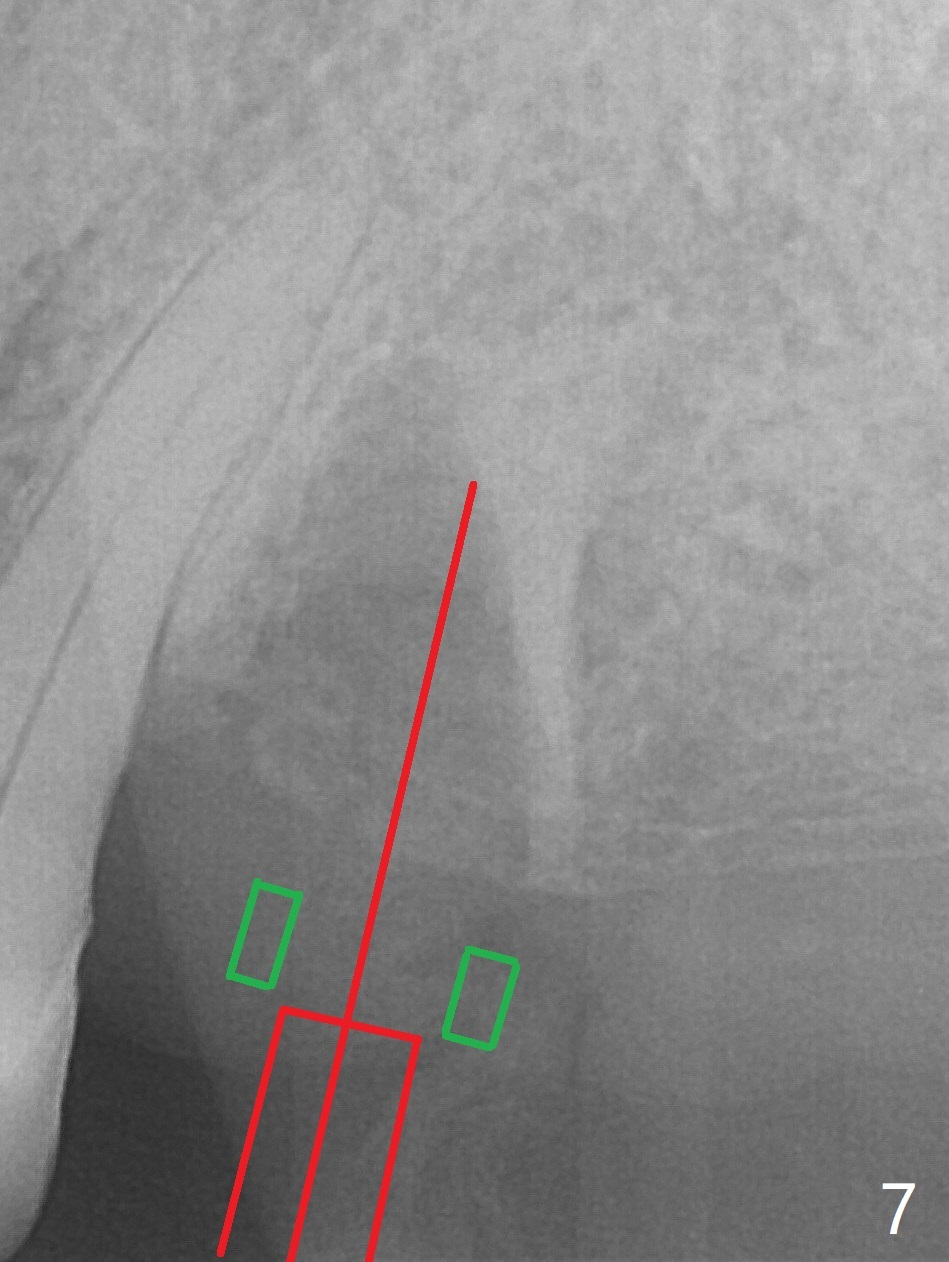

After extraction of the tooth #13 residual root, the bone in the distal wall of the socket looks white. Intraop PA rules out root structure (Fig.1 *). Osteotomy is conducted according to drill sequence. Bitewings are taken to check implant placement level (Fig.2,3). Following implant level adjustment and healing abutment installment (Fig.4,5 (*: bone graft)), the implant at #13 is found to be close the root of #12 (Fig.6 *), i.e., not parallel to the implant at #14. Introspectively, 2.2x10 mm drill seems to be long. When it touches the bone, the cylinder portion of the drill (Fig.7 red) does not engage into the sleeve (green). When it goes into the bone, it may have been deflected mesial due to the slope of the distal wall of the socket (hard bone, Fig.8 open arrow)). If a shorter drill (such as 2.2x7.3 or 8.5 mm) were used (Fig.9), the deflection would be minimal if drilling is slow (Fig.10). CT taken 1 week postop shows that the implant at #13 is approximately 1 mm near the root of the tooth #12, but the neurovascular bundle to the latter seems not to have been interrupted (Fig.11,12). The buccopalatal trajectory at #14 is within normal limit (Fig.11,13 (B: buccal)). There is no periapical radiolucency at #12 five months postop (Fig.14). However the cemented abutments are incompletely seated (<). The patient is reluctant to return for impression 17 months postop (due to coronavirus); with attention, the same abutment at #13 is reseated completely; an abutment with longer cuff and narrower diameter is also seated completely (Fig.15).